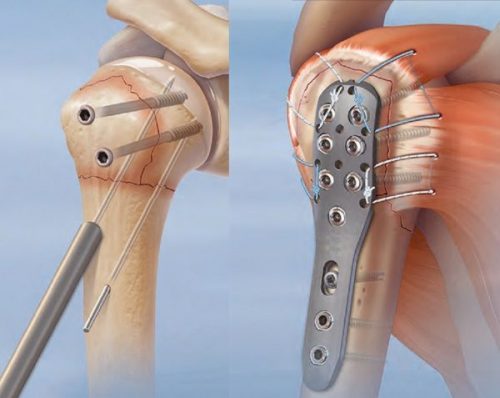

Что это такое

На современном этапе в травматологии используются самые разные варианты пластин. Они могут иметь различную форму, что обусловлено участком кости, куда они должны быть установлены. Существенные различия имеют отверстия, в которых винт за счет шляпки надежно фиксирует перелом.

Все пластины имеют определенные функции:

- восстановление нормальной анатомии кости;

- ускорение сращения;

- ранняя нагрузка на прооперированный участок.

Но для того, чтобы установить пластину на кость требуется большое количество инструментов. И они были разработаны, благодаря чему операция проходит быстрее.

Если у больного диагностирован внутрисуставный перелом локтевого отростка, лучше всего провести операцию по установке металлоконструкций. Процедура проводится сразу же после травмы. Остеосинтез локтевого отростка требует фиксации отломков, но перед этой манипуляцией медику нужно будет полностью устранить смещение. Гипс пациент носит 4 и более недель, так как это место тяжело поддается лечению.

Одна из самых популярных методик проведения остеосинтеза — сращивание по Веберу. Для этого специалист использует титановую спицу (2 шт.) и проволоку, из которой делают специальную петлю. Но в большинстве случаев подвижность конечности будет ограничена навсегда.

Остеосинтез лодыжки показан при наличии большого количества раздробленных, винтообразных, ротационных, отрывных или оскольчатых переломов. Операция требует обязательного предварительного снимка рентгена, а иногда нужна томография и МРТ. Закрытый тип повреждения сращивают с помощью аппарата Илизарова и вводят спицы в поврежденное место.